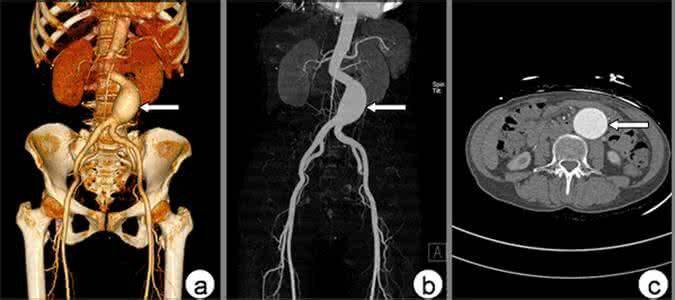

3.CT血管成像(CTA)

是腹主动脉瘤最常用的检查手段,与超声检查相比,可以更清晰地显示腹主动脉瘤的全貌及其与周围组织结构如肾动脉、腹膜后及脊柱的关系,以及腹膜后血肿等。其诊断准确率几乎达100%。